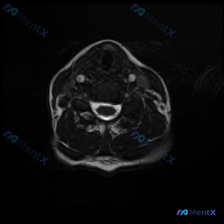

看到一个有意思的读片病例,整理了完整的分析思路分享给大家。 病例基本信息 核心问题:临床怀疑颈椎间盘病变,提供单张颈部MRI T2加权轴位影像,请判断病变情况。 影像学观察结果 这张图像是颈椎中下段水平的标准T2加权轴位影像,对比度良好无明显运动伪影,影像观察结果如下: 1. 椎间盘与骨性结构: 椎...